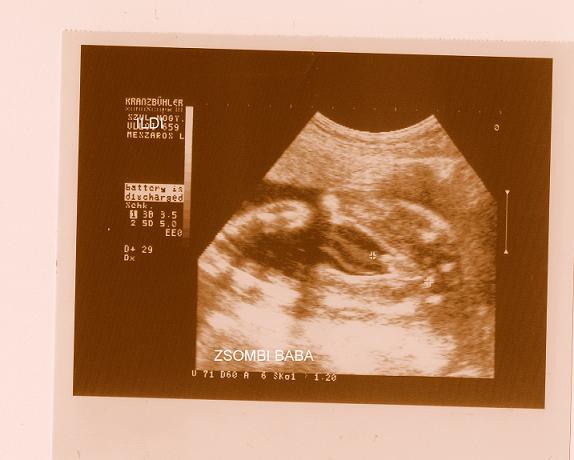

gratula Zsombihoz!

Gratulálok Zsombor babához!

Ez a név nálunk is esélyes volt!

Sziasztok !Akkor most megmutatjuk a Fütyinket :D :D :D :D :D :D Kép

...ja , balra 2 karocska, arc eltakarva, jobbra lábak széttéve ééééés középen egy naaaaagy fütyi :D :D :D